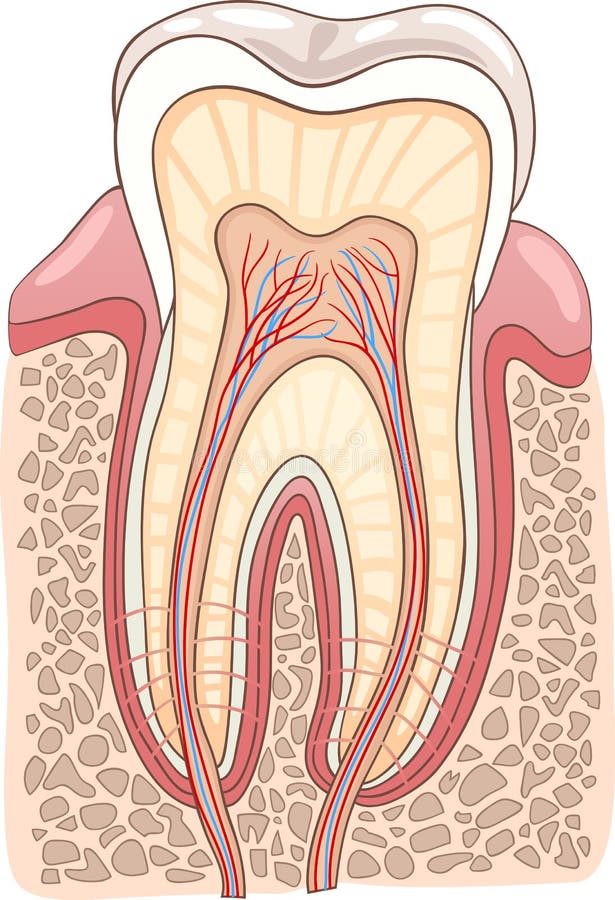

Tanden strukturerar Medicinskt diagram av strukturen av det inre tvärsnittet av tanden